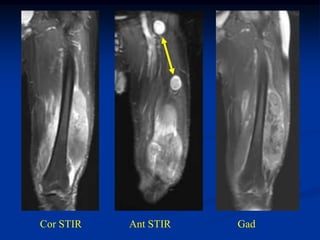

Case #259.2                   MFH with skip lesions

64 year male with painful soft tissue mass in thigh for 6 mos

Cor STIR   Ant STIR   Gad

Axial T-2   Lower T-2

Lower Gad

Sag Gad   Gad